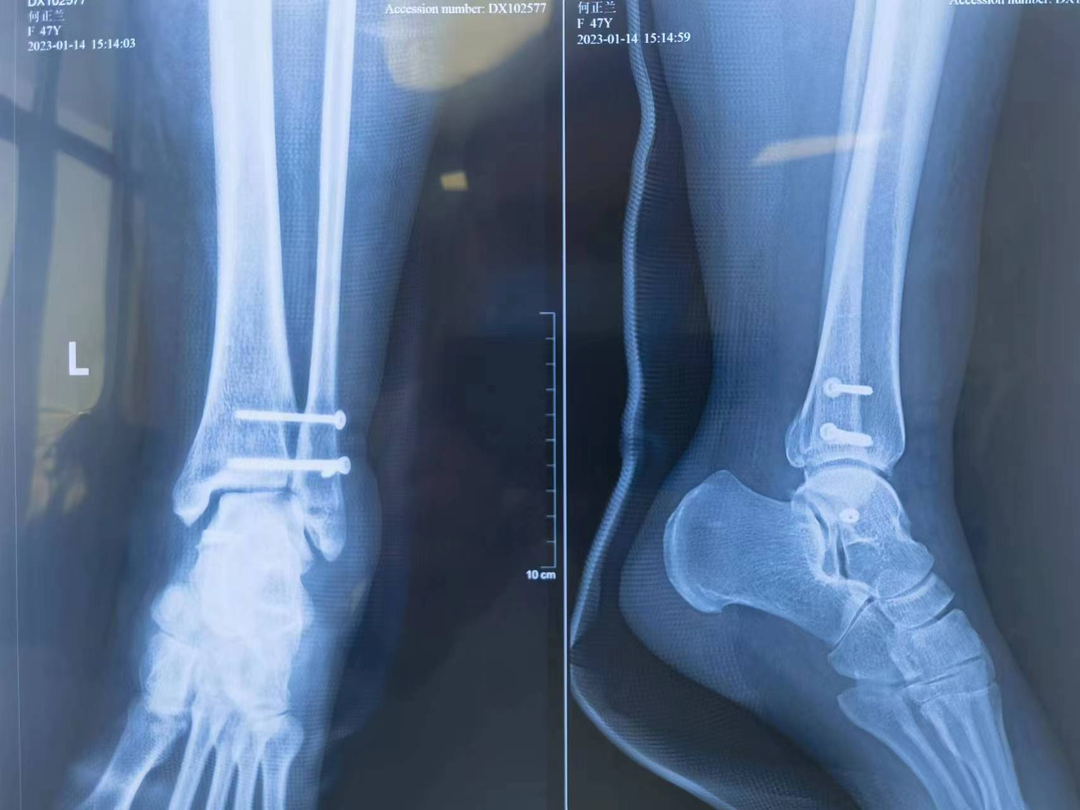

近日,我院急诊收治一名踝关节扭伤病人,患者女性,47岁,就诊时踝关节肿胀较严重,疼痛剧烈,活动受限,查体因疼痛不能完成。 急诊踝关节摄片提示:左踝关节脱位。当晚值班医师立即汇报骨科梁永新主任,根据患者扭伤机制,梁主任指示该患者为一种特殊类型的踝关节骨折(Maisonneuve骨折)。此类病例极易漏诊,患者常合并有腓骨近端骨折、后踝骨折、下胫腓前韧带损伤、三角韧带损伤。需立即完善膝关节DR检查及踝关节三维重建CT。 (术前DR) 明确并支持诊断,向患者交代病情,因患者日常活动量较大,需手术治疗完全纠正踝关节脱位,并对踝关节下胫腓前韧带、内踝三角韧带进行修补。修补后的韧带强度远大于疤痕愈合的强度,能最大程度减轻或避免踝关节创伤性关节炎的发生,患者考虑后表示同意,立即办理入院手续。 入院后,梁永新主任对其予以下肢石膏托中立位外固定、冰敷、改善血液循环、止痛等对症处理。第5天,梁主任经过术前充分评估,同患者及其家属充分沟通后,协同麻醉科沈智勇主任,骨科团队单金平、周奇凡医师共同完成手术。术中探查后发现与术前诊断完全一致,予以逐一修补,术中摄片提示踝关节脱位完全纠正,手术过程十分顺利。患者术后第2天,在陈锡丰护士长率领的护理团队的精心指导下下床不负重活动。术后1周办理出院,患者对于手术效果非常满意。 (术后复查DR、CT) (术后三天伤口) 梁永新个人简介 梁永新,中共党员,硕士研究生,副主任医师,2003年毕业于新疆医科大学临床医学院,2009年于新疆医科大学取得肿瘤学硕士学位,现任盐城市大丰区第三人民医院骨科主任,乌鲁木齐市工伤鉴定专家组成员。 从事骨科临床及相关研究工作17年,并长期开展规培生授课、带教、乌鲁木齐市级工伤鉴定等工作。擅长骨与关节、运动医学、创伤、脊柱退行性疾病、小儿骨科的诊治,主要开展肩、膝、踝关节镜、关节置换、创伤、脊柱、小儿骨科等手术。 读研期间在新疆维吾尔自治区人民医院骨科学习创伤骨科、新疆医科大学附属肿瘤医院学习骨肿瘤诊治;工作期间曾赴广东省人民医院骨科进修学习关节与运动医学;硕士研究生毕业后曾在乌鲁木齐市友谊医院骨科、乌鲁木齐市第一人民医院骨科等三甲医院工作。 在国家级核心期刊发表论文3篇(第一作者),省级核心期刊发表论文5篇(第一作者),出版骨科专著1本(副主编),取得国家级实用型专利1项,参与完成乌鲁木齐市级科研课题1项。